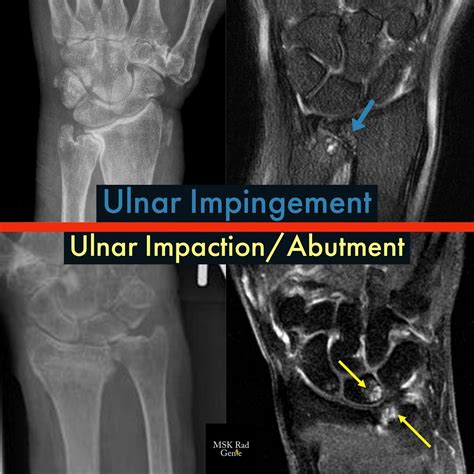

At its core, Ulnar Impaction Syndrome is a degenerative condition characterized by the mechanical abutment of the distal ulna—the bone on the pinky side of your forearm—against the bones in the wrist (specifically the lunate and triquetrum) and the triangular fibrocartilage complex (TFCC). In a healthy wrist, the radius and ulna work in harmony to support the carpal bones. However, if the ulna is relatively longer than the radius, a condition called “ulna positive variance,” it creates a crowded space that leads to repetitive grinding, cartilage wear, and ligament tears.

Imaging is equally vital. Standard X-rays, particularly those taken in a neutral position, help clinicians measure the ulnar variance. In more complex cases, an MRI is ordered to evaluate the extent of TFCC damage, cartilage wear on the lunate, or subchondral bone edema, which is the "bruising" of the bone caused by persistent impaction.